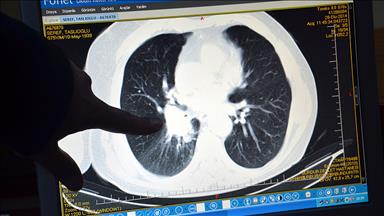

Sigara kullanımının üreme sağlığı üzerindeki etkisini ortaya koyan bilimsel çalışmalar, tütün ve tütün ürünlerinin tüketilmesinin düşük riskini yüzde 39, dış gebelik riskini yüzde 27, kısırlık riskini yüzde 22, erken menopoz riskini yüzde 17 artırdığını gösterdi.

Prof. Dr. Gürgan, Amerikan Üreme Tıbbı Cemiyeti verilerine göre, ülkede üreme çağındaki kadınların yüzde 30'unun, erkeklerin ise yüzde 35'inin sigara kullandığını söyledi. Gürgan, "Sigara kullanımı, düşük riskini yüzde 39, dış gebelik riskini yüzde 27, kısırlık riskini yüzde 22, erken menopoz riskini yüzde 17 artırıyor." diye konuştu.

Hacettepe Üniversitesince yapılan bir araştırmaya göre, tütün kullanımının kadınların yüzde 13'ünde kısırlığa (infertilite) neden olduğunun ortaya konduğunu dile getiren Gürgan, "Günlük içilen sigara miktarına bağlı olarak spermin yoğunluğunu ortalama yüzde 22 oranında azalıyor." bilgisini verdi.

Sigara kullananlarda tüp bebek uygulamalarında başarı oranlarının da azaldığını ifade eden Gürgan, "Oluşan gebeliklerin düşükle sonlanma riski artıyor. Sperm hareketliliği azalıyor ve şekil bozukluğu gelişebiliyor. Önemli olan şey ise sigarayı bıraktıktan sonra hem erkek hem de kadınlarda üreme yetisinin güçlenmesidir." sözlerine yer verdi.